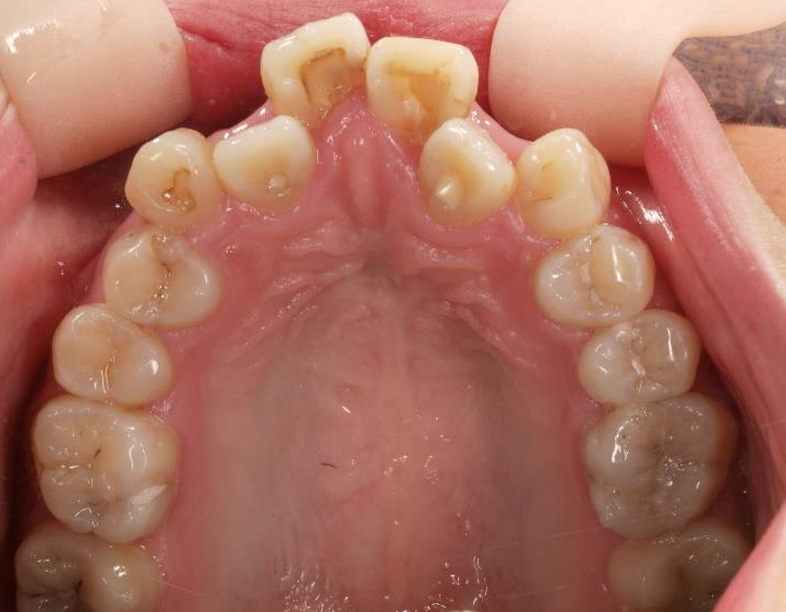

乱ぐい歯、でこぼこがとても酷い状態になります。歯が前後的に重なってしまっている、八重歯になっているなどがこのジャンルに入ります。

顎の大きさと歯の大きさのギャップが大きく、時には歯を抜かないと矯正治療ができない場合もあります。当院では治療期間が長くなるが抜かない治療方針など、一つの治療プランだけでなく、さまざまな可能性の治療方針を説明させて頂くよう心掛けております。こういった考え方はインフォームド・チョイスと言われ近年大切にされている考え方と言われております。

治療前

治療終了前